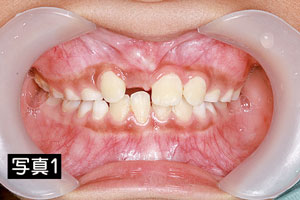

9歳の男の子、右前歯が生えてこないと来院されました。【写真1】